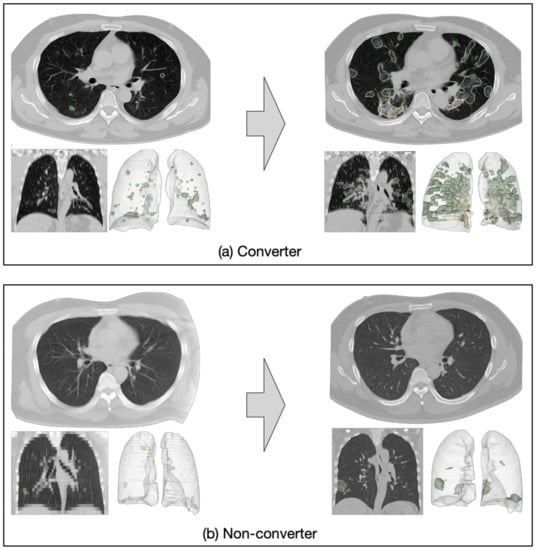

The second goal of this study is to predict disease progression for the mild/ordinary cases based on their baseline CT scans. In other words, we aim to predict which of the mild/ordinary severity patients are likely to progress to the severe/critical category (converter class) in the short term (within seven days), and which patients would remain stable or recover (non-converter class), based on the assumption that lesion features may carry important prognostic information for forecasting disease progression. We again consider the task as a binary classification problem (i.e., to classify the non-converter cases and converter cases). Figure 1a presents an example of a COVID-19 case with mild symptoms. In less than seven days, the patient’s symptoms rapidly worsened and progressed to severe. Figure 1b is an example of a non-converter case whose symptoms progressed slowly and remained mild seven days after the baseline CT scan.

Figure 1. Examples of converter and non-converter cases. (a) A mild case progressed to severe within seven days; (b) a mild case did not progress to severe within seven days.